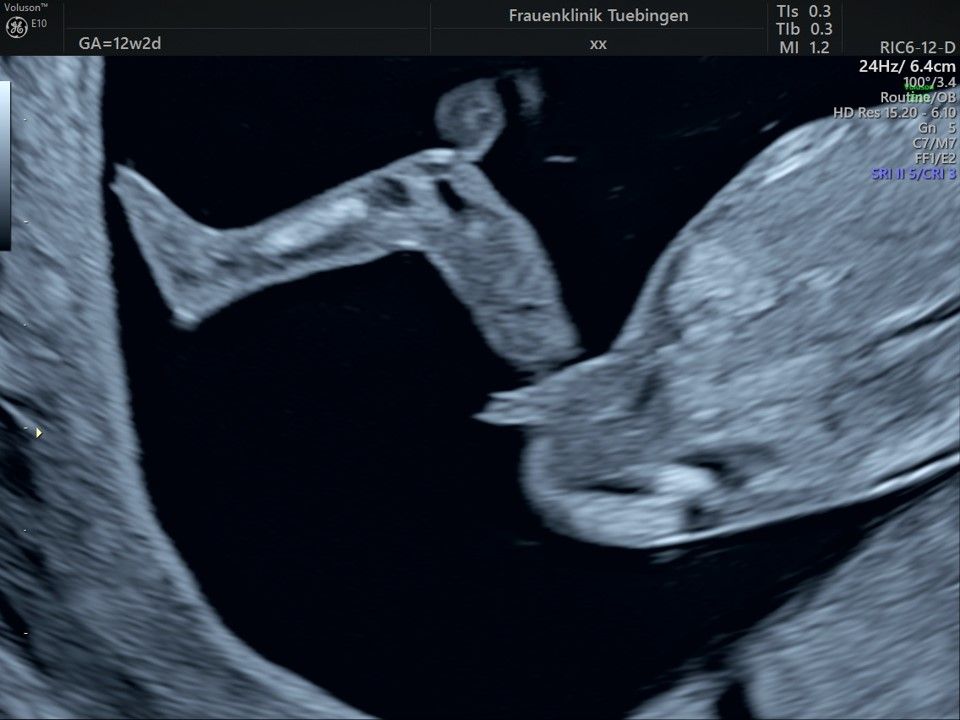

Im Rahmen des Ersttrimester-Screenings untersuchen wir die Organe des Feten mittels Ultraschall. Dabei machen wir auch gerne ein Bild für Sie.

Obwohl der Fet zu diesem Zeitpunkt erst zwischen 5 und 8cm groß ist, lassen sich bereits etwa die Hälfte aller schwerwiegenden Fehlbildungen erkennen bzw. ausschließen. Sollten wir eine Auffälligkeit sehen, werden wir mit Ihnen den Befund und das weitere Vorgehen ausführlich besprechen.

Die eigentliche Organuntersuchung findet um die 20.SSW (zweites Screening) statt. Das Ersttrimester-Screening und das zweite Screening sind sich ergänzende Untersuchungen und ersetzen sich gegenseitig nicht.